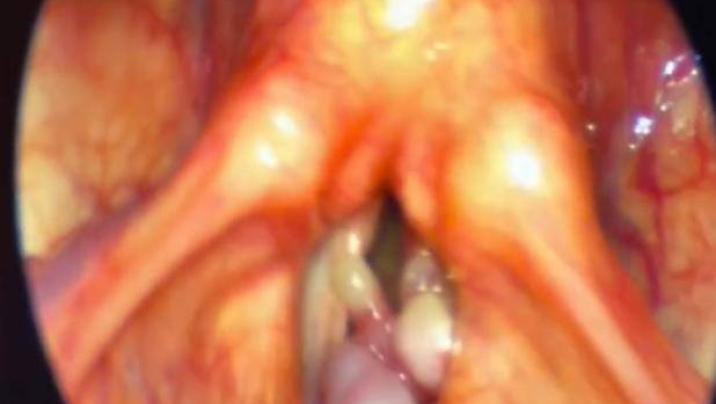

Müayinə zamanı bir lor cərrah xəstənin bütün sol səs telinin böyük bir şiş tərəfindən tutulduğunu aşkar edib. Kişi təcili əməliyyat keçirib və bundan sonra toxuma nümunəsi analiz üçün göndərilib. Həkimlər artıq son qərarlarını veriblər ki, siqaretlər, veyplər və digər qızdırılan tütün sistemləri həmişəlik tərk ediləcək.